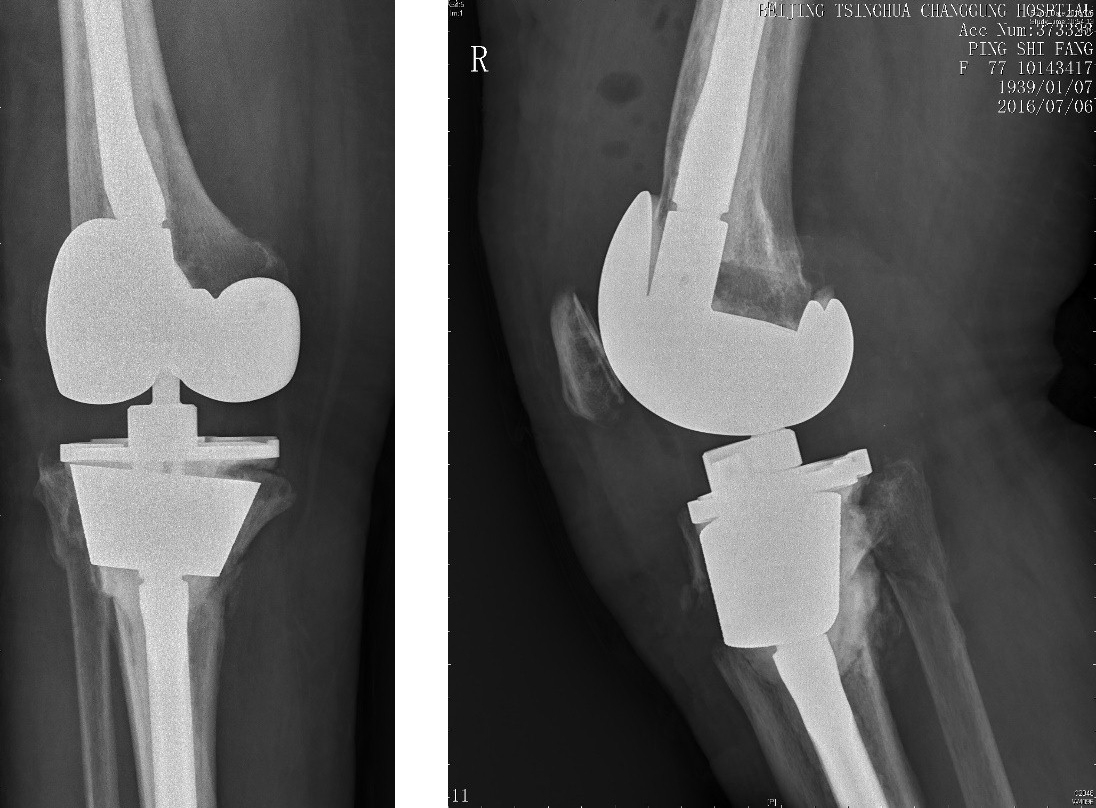

蔡谞教授对该患者进行了仔细的评估,通过平片可以看出假体柄松动严重合并有严重的骨溶解、胫骨干骺端有腔洞样或节段性骨缺损,手术难度极大。蔡谞教授将治疗目标定在维持满意的肢体力线,膝关节稳定,骨折愈合上,在上述基础上实现关节功能良好恢复。在排除了血管神经等组织损伤后,蔡主任综合考虑了假体有无松动、骨折的类型和部位、是否骨水泥固定、患者的体质与精神状况等多项因素后决定采用加长柄假体结合填充性或结构性植骨的治疗方案,同时制定备用方案以防最初制定的手术方案不能实施。同时在骨折治疗的同时,也要强调术后对骨质疏松症的治疗,以有效降低骨折延迟愈合、不愈合的风险,防止骨折的再次发生。

术前平片——显示为Felix IIB型 胫骨平台假体周围骨折

胫骨假体柄松动合并有严重的骨溶解、胫骨干骺端有腔洞样或节段性骨缺损